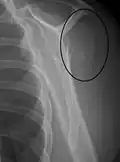

Proximal humerus fracture -

A transverse fracture of the humerus shaft -